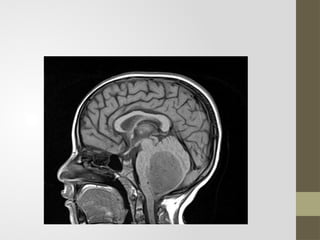

MRI features of a mixed solid and cystic tumor of the right

cerebellum suggestive of a pilocytic astrocytoma (pathologically

proven).

• The patient went to have a resection of the tumor with

histopathological exam which confirmed the diagnosis of a

pilocytic astrocytoma grade I